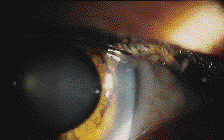

Contact Lens Acute Red Eye (CLARE)

Some patients who overwear their soft lenses or who sleep in lenses not intended for overnight wear may present with frank corneal abrasion or erosion such as appears with hard contact lens overwear syndrome. Other patients may present with symptoms of pain, photophobia, and intense perilimbal injection, but no evidence of frank epithelial abrasion. This condition has been referred to as contact lens acute red eye, or CLARE (Fig. 1). Other associated clinical signs include corneal epithelial edema, conjunctival injection and limbal edema, as well as limbal infiltrates in the peripheral cornea (Fig. 2). The etiology of CLARE is not well understood, but it is believed to be related to the body's immune response to corneal hypoxia. Brien Holden, Ph.D., and others have postulated that the hypoxic corneal epithelium produces a substance that leads to inflammation and leukocyte infiltration. The breakdown of any cell membrane releases membrane phospholipids that are converted into arachidonic acid. This is then converted into prostaglandins by cyclooxygenase and leukotrienes by lipoxygenase. Prostaglandins, particularly PGE2, lead to inflammation, and leukotrienes are chemotactic (attract leukocytes). This may be the final common pathway.